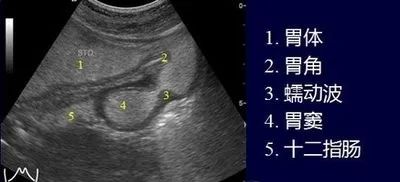

• 超声波精准成像:消除胃内气体干扰,清晰显示胃壁 5 层结构(黏膜层至浆膜层)及病变范围

• 动态观察全程无痛:无需麻醉、不插管,医生通过体外扫描即可实时评估胃蠕动、排空功能